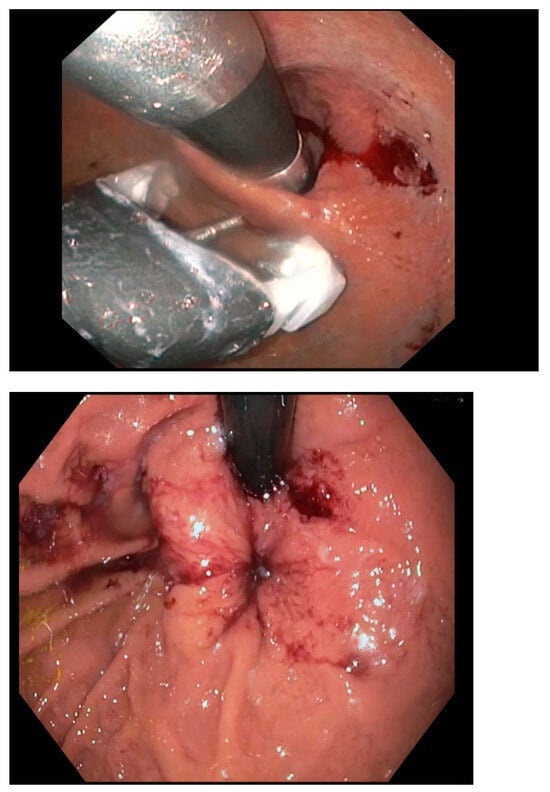

- TIF: TIF is typically performed using the EsophyX (Endogastric Solutions, Merit Medical, UT, USA)) device, which uses fasteners to create folds in the stomach at the gastroesophageal junction. The goal is to reconstruct the valve-like function of the lower esophageal sphincter (LES) by creating a tighter anti-reflux barrier. TIF involves the creation of a 270–300° fundoplication, making it less invasive than traditional fundoplication surgery.

- EFTP: EFTP, by contrast, involves the use of transmural sutures, which go through the entire thickness of the stomach wall to secure the plications. This technique aims to improve LES function by placing full-thickness sutures at specific points to bolster the gastroesophageal junction’s barrier. Because it penetrates deeper layers of the tissue, EFTP can offer a more robust structural alteration. Endoscopic full-thickness plication is performed using the GERDx™ system (G-SURG GmbH, Seeon-Seebruck, Germany). The GERDx™ system is the advanced single use product of a company that has taken over the Plicator technology, after the Plicator device (Ethicon Endosurgery, Sommerville, NJ, USA) was taken off the market